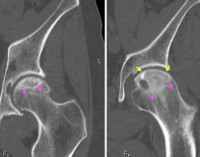

• Рентгенография тазобедренного сустава в 3 проекциях. Этот метод помогает определить наличие АНКБК и стадию заболевания. Однако на первой стадии рентгенологические признаки некроза головки бедра могут отсутствовать, что может привести к диагностической ошибке. Поэтому рекомендуется повторить рентген через полгода.

• КТ. Применяется для получения послойных изображений тазобедренного сустава и изучения особенностей кровотока.

• МРТ. Позволяет выявить малейшие изменения в состоянии сустава, особенно в гиалиновых хрящах и мягкотканевых структурах.